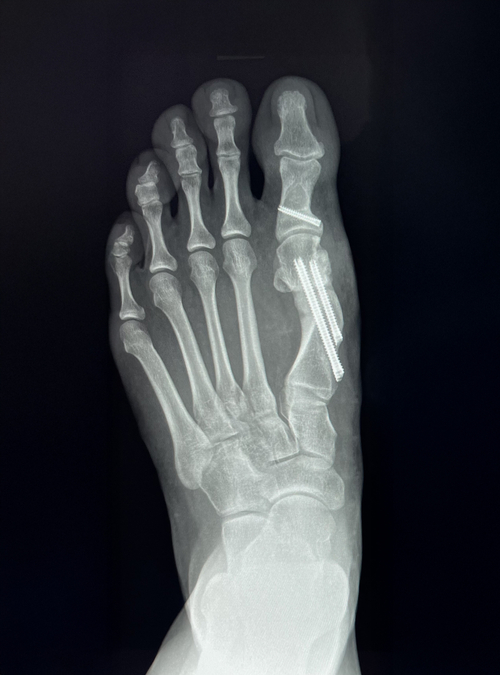

All bunion cases are best assessed by an orthopaedic consultant who specialises in foot and ankle conditions. Their treatment plan is often formed by using images such as X-rays or sometimes an MRI scan. At HCA UK we can offer a variety of treatments, including conservative options which don’t involve surgery, depending on the pain level and how your foot looks. Having an expert discuss your options with you can be very helpful.

x-ray 1.jpg x-ray 2.jpg

In my keyhole bunion surgery, I make small incisions in the skin, break the bones either side of the big toe joint, which is called an osteotomy, and then push these into a better position before fixing them with screws. These screws generally stay in and do not need to be removed, though they can be if necessary.